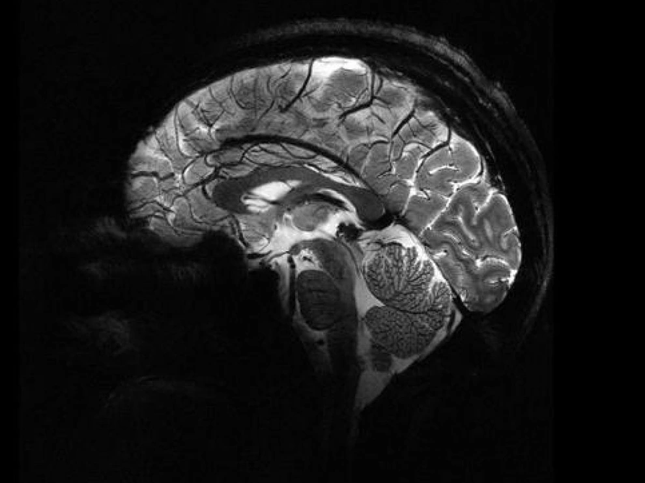

Bộ não người chụp từ máy quét MRI Iseult (Ảnh: CEA).

Những hình ảnh lịch sử này được chụp từ máy quét MRI Iseult, chụp cộng hưởng từ, trong trung tâm nghiên cứu CEA, Ủy ban Năng lượng Nguyên tử Pháp.

Với những hình ảnh này, chúng ta có thể thấy những chi tiết khá ngoạn mục. Nó cho chúng ta biết về các chi tiết giải phẫu như tĩnh mạch hoặc các lớp vỏ não mà trước đây không thể đạt được".

Nhờ máy quét MRI Iseult, các nhà nghiên cứu có thể bóc tách bộ não của chúng ta với độ chính xác đáng kinh ngạc: khoảng một phần trăm triệu mét hay độ dày của bốn sợi tóc.

Nhà nghiên cứu Anne Isabelle Etienvre (CEA), cho biết, cỗ máy này tạo ra từ trường kỷ lục (11,7 đơn vị Tesla), gấp 230.000 lần từ trường Trái Đất. Lưu ý rằng, từ trường càng cao thì độ phân giải của hình ảnh càng lớn.